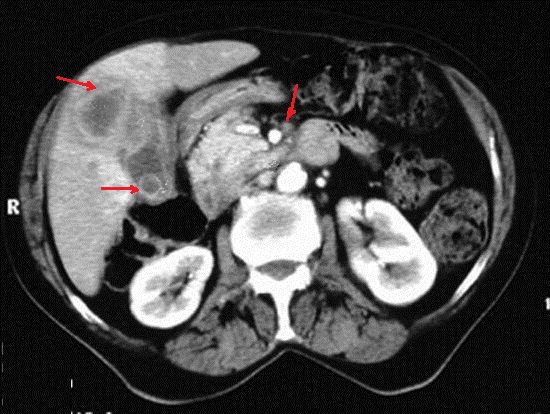

Image TDM + contrast intraveineuse en

coupe axiale : Aspect d'une adenomecarcinoma de la

vesicule biliaire , epaissisement de la paroi et

image de lesion infitrative au bas de la vesicule ,

rehaussement par de contrast ( fleche rouge ) .

Image de calcul arrondie hyperdense a infundibulum

est tres nette . Adenopathie hilaire hepatique et

coeliomesenterique est encore se presente |